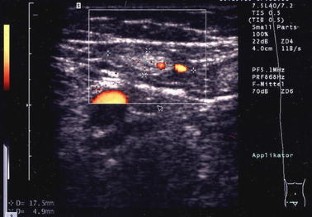

In 55 patients, 40 lymph nodes were correctly categorized as benign and 15 lymph nodes correctly as malignant. The most reliable criteria were shape and vascularization pattern. Intact hilar vessels and branching indicated benign enlargement, destruction of the hilum with vessels running peripherally along the capsule indicated metastatic destruction. Two benign lymph nodes were considered malignant (false positive).

Abb. 4